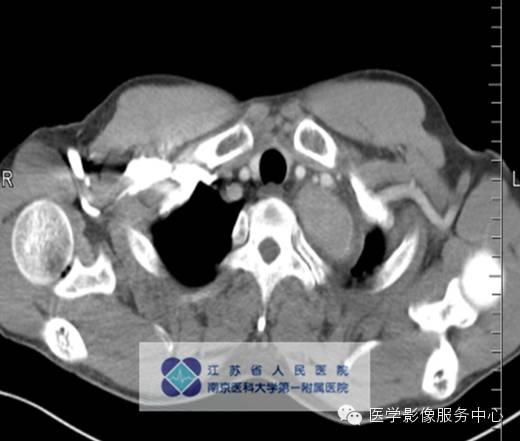

男,27岁,因“查体发现纵隔占位三月余”入院。

影像分析:左上、后纵隔内见类圆形软组织密度增高影,密度尚均匀,边缘清晰,增强扫描均匀强化。